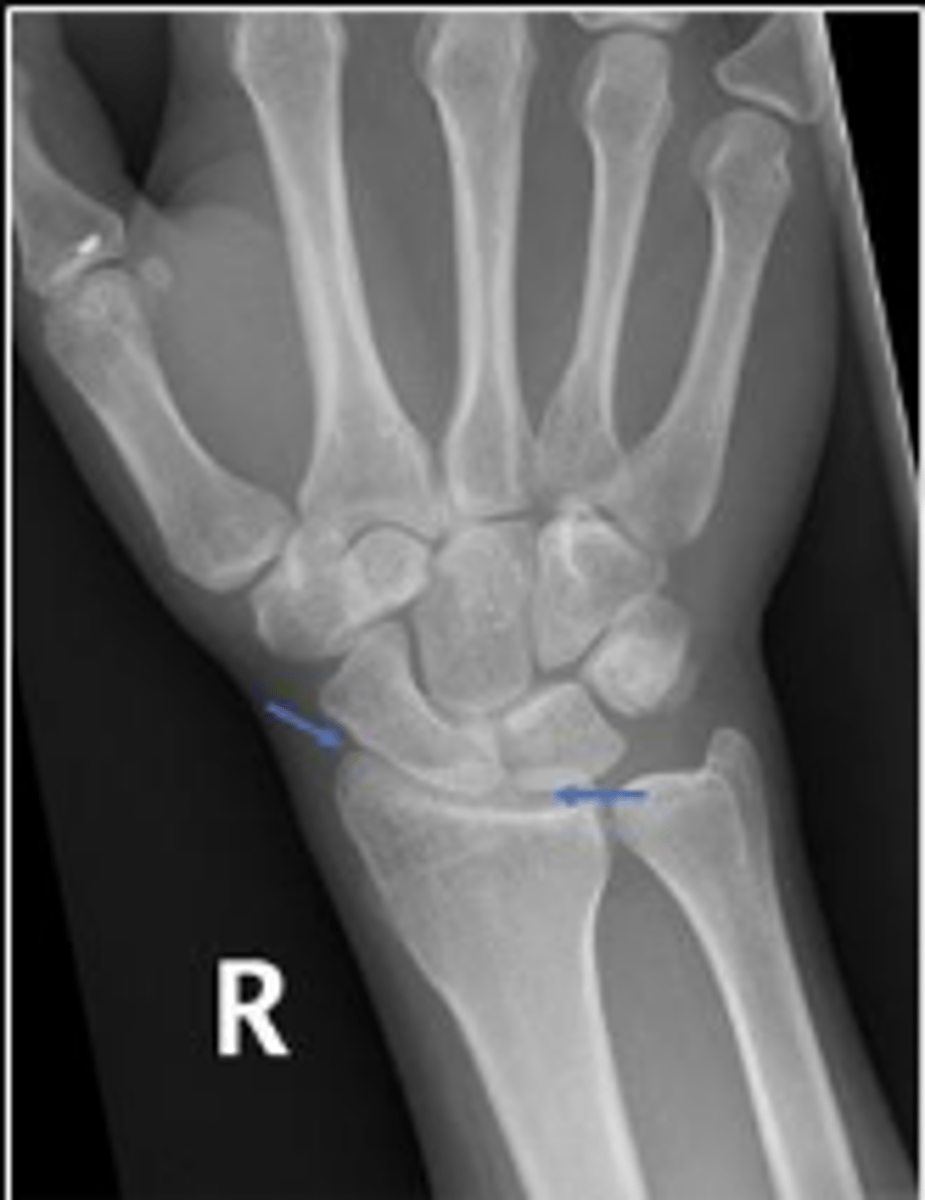

Medial oblique of the right wrist

What is the name of the radiographic view?

Right triquetrum

What is outlined?

Right pisiform

What is the arow pointing to?

DRUJ

What is the arrow pointing to?

< and equal to 2mm

What is the normal measurement of this space?

What are the arrows pointing to?

Right radiocarpal joint

What joint space are the arrows pointing to?